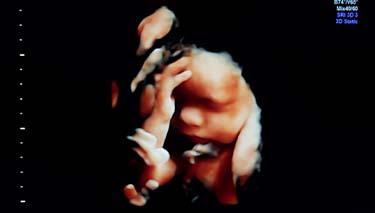

Yes, you ll be amazed at what detail the ultrasound will provide. Be prepared to feel very connected with your baby and perhaps overwhelmed by feelings of love. Many mothers cry when they see their baby in such a realistic way and partners can feel similar feelings as well. For partners who've not experienced pregnancy symptoms first hand, seeing their baby on an ultrasound screen can the first time they really, truly believe the baby exists. Not that this is a commonly discussed issue but it is still a fact.

It's common for expectant parents to be given a photo of their 20 week ultrasound. This can be viewed later on at your own leisure and if you want to, shared with your friends and family. It has become routine for imaging centres to request parents that no photographs or videos are taken during ultrasounds and any recordings or images can only be supplied by the sonography service.